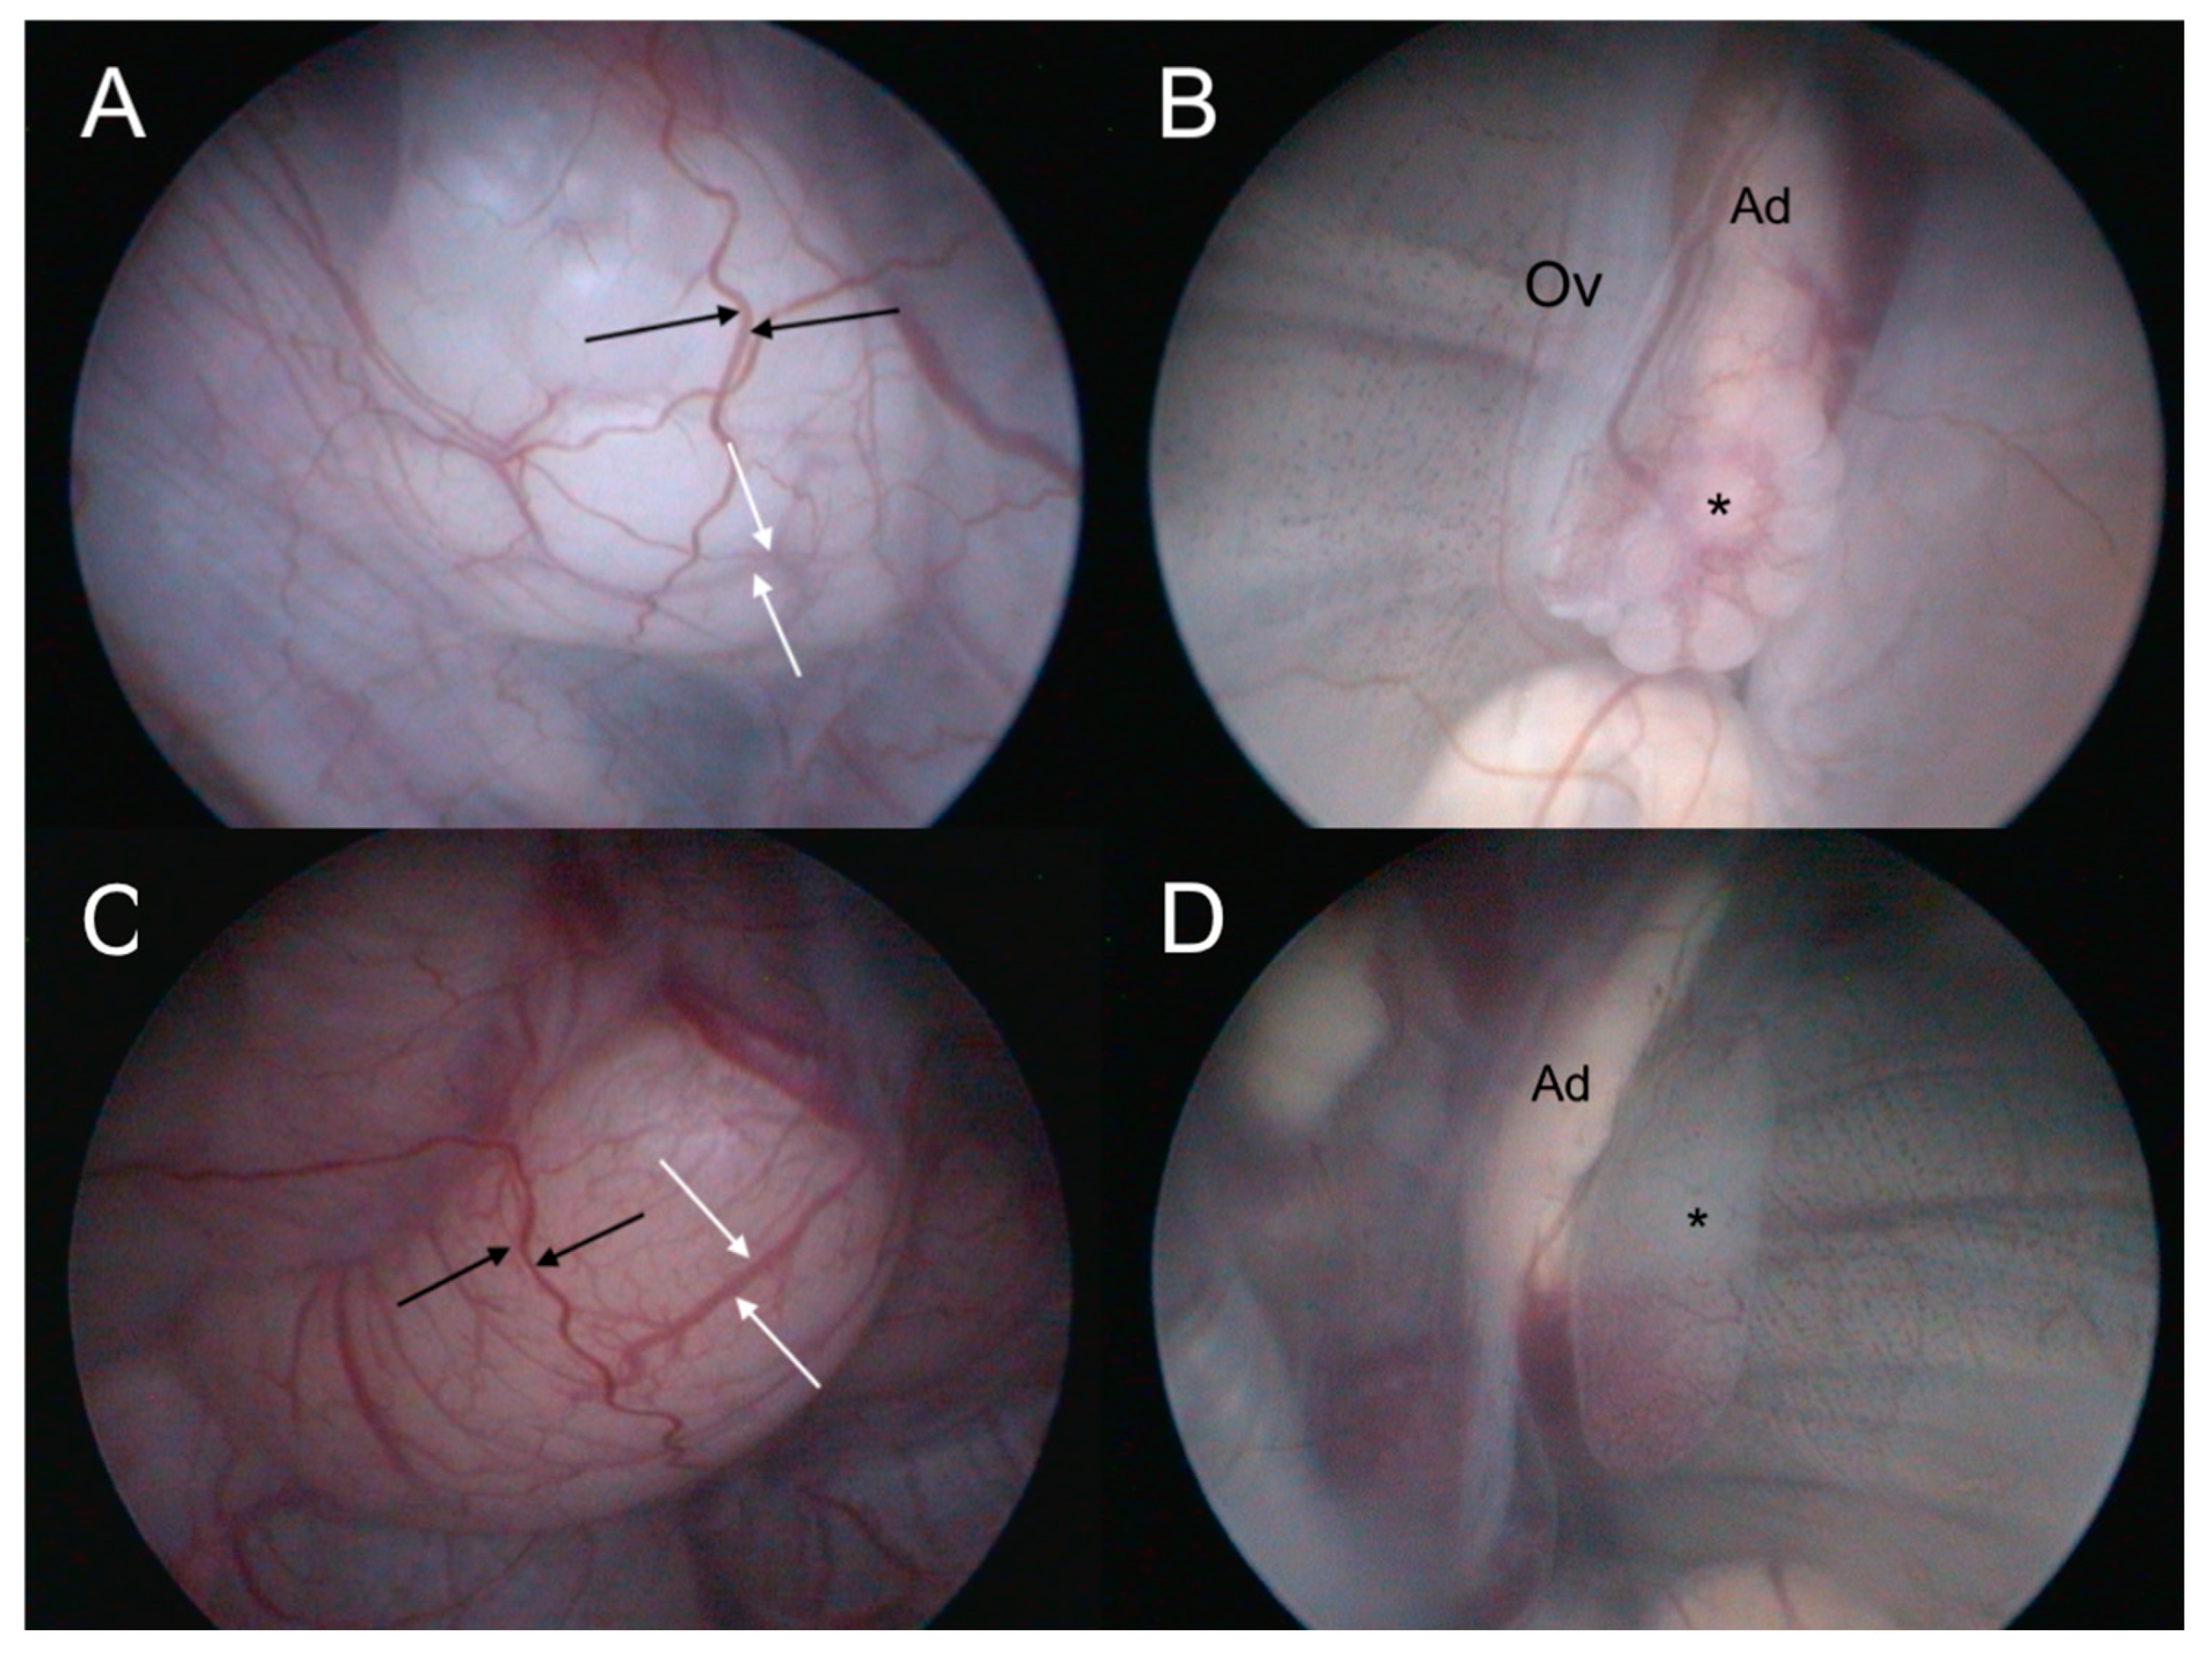

5.9. Coelioscopy

5.10. Cystoscopy

5.11. Cloacoscopy